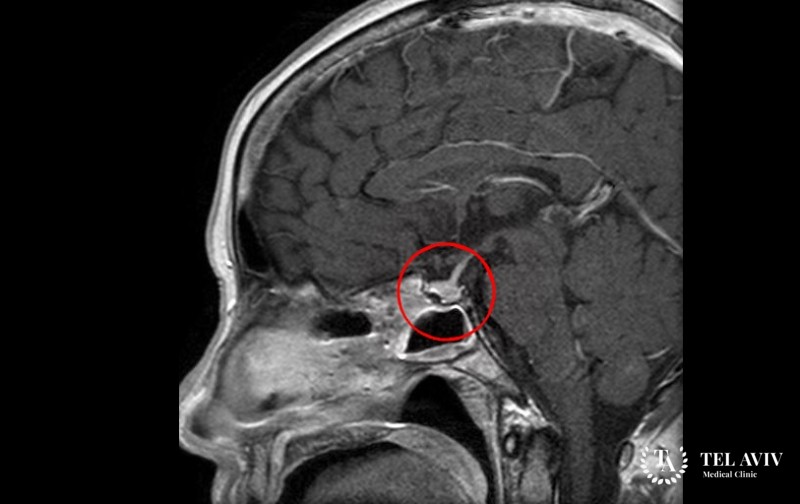

Первичная диагностика кортикотропиномы заключается в сборе анамнеза. Больному необходимо посетить несколько специалистов узкого профиля, сдать кровь на анализ. Специалисты определяют количество гормонов в крови: калий, кортизол, натрий, глюкозу. Обследование включает:

- Магнитный резонанс;

- Ядерную, магнитную томографию;

При необходимо специалист использует контрастное вещество в ходе проведения компьютерной томографии.